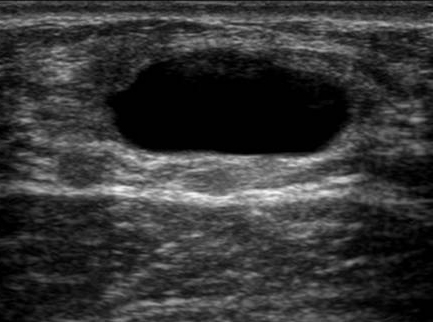

Quiste Simple de Mama

Caso Clínico- .-No poseer ningún eco interno

- .-Su forma debe ser redonda u oval

- .-Debe ser de contornos lisos

- .-debe tener refuerzo acústico posterior.